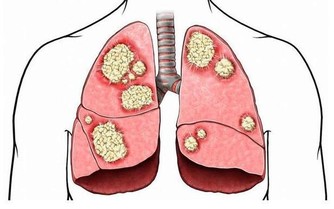

在兒童腫瘤數據中,超過一半的數據由白血病“貢獻”,而且還在以每年3-4萬的速度往上增加。在治療的同時我們也在深思,為什麼受傷的總是孩子?

孩子身體有效,但是細胞很活躍,代謝和更新的速度比成年人快,如果外界環境中存在不良因素,細胞在分裂的過程中就可能“出差錯”,最後形成癌細胞。

四種表現暗示白血病到來,不可當成小病一直“拖”

醫生提醒:孩子貧血沒有精神、頻繁發燒降不下來、鼻腔牙齦莫名出血、關節疼痛水腫,這些都可能暗示白血病到來,若是經過用藥還沒有緩解,就不要再拖下去了,盡快就醫檢查。